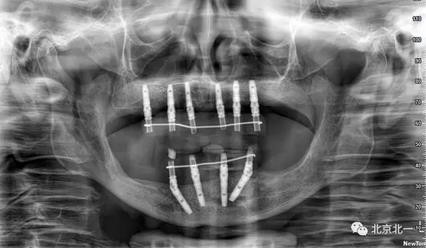

術(shù)后CBCT檢查,位置方向理想位置。

1,精準(zhǔn)度更佳,通過(guò)導(dǎo)板技術(shù)將種植體放置在預(yù)先設(shè)定的位置,十分精準(zhǔn)。

2.安全性保障,軟件輔助,避免血管神經(jīng)。在同一個(gè)病人之下,建立不同的治療方案,術(shù)前精確設(shè)計(jì),術(shù)中精準(zhǔn)控制。